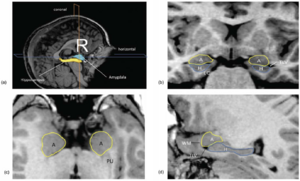

Potential of Diffusion Tensor Imaging and Relaxometry for the Detection of Specific Pathological Alterations in Parkinson's Disease (PD)

Publication: PLoS One. 2015 Dec 29;10(12):e0145493. PMID: 26713760 | PDF Authors: Esterhammer R, Seppi K, Reiter E, Pinter B, Mueller C, Kremser C, Zitzelsberger T, Nocker M, Scherfler C, Poewe W, Schocke M. Institution: Department of Radiology, University Hospital, Innsbruck Medical University, Innsbruck, Austria. Background/Purpose: The purpose of the present study was to evaluate the potential of multimodal MR imaging including mean diffusivity (MD), fractional anisotropy (FA), relaxation rates R2 and R2* to detect disease specific alterations in Parkinson's Disease (PD). We enrolled 82 PD patients (PD-all) with varying disease durations (≤5 years: PD≤5, n = 43; >5 years: PD>5, n = 39) and 38 matched healthy controls (HC), receiving diffusion tensor imaging as well as R2 and R2* relaxometry calculated from multi-echo T2*-weighted and dual-echo TSE imaging, respectively. ROIs were drawn to delineate caudate nucleus (CN), putamen (PU), globus pallidus (GP) and substantia nigra (SN) on the co-registered maps. The SN was divided in 3 descending levels (SL 1-3). The most significant parameters were used for a flexible discrimination analysis (FDA) in a training collective consisting of 25 randomized subjects from each group in order to predict the classification of remaining subjects. PD-all showed significant increases in MD, R2 and R2* within SN and its subregions as well as in MD and R2* within different basal ganglia regions. Compared to the HC group, the PD≤5 and the PD>5 group showed significant MD increases within the SN and its lower two subregions, while the PD≤5 group exhibited significant increases in R2 and R2* within SN and its subregions, and tended to elevation within the basal ganglia. The PD>5 group had significantly increased MD in PU and GP, whereas the PD≤5 group presented normal MD within the basal ganglia. FDA achieved right classification in 84% of study participants. Micro-structural damage affects primarily the SN of PD patients and in later disease stages the basal ganglia. Iron contents of PU, GP and SN are increased at early disease stages of PD. Funding:

The regions-of-interest (ROIs) were manually drawn by an experienced radiologist by using the b 1000 images, averaged for all measured directions, the FA maps and the proton-density weighted images. For that purpose, the maps of ADC, FA, R2 and R2* as well as the proton-density weighted images were first co-registered. The ROIs were segmented by syncing the b 1000 images, averaged for all measured directions, the FA maps and the proton-density weighted images in ImageJ. The ROIs were stored in the ROI manager and transferred to the co-registered maps. The segmented brain regions were highlighted in different colors: CN—black; PU—red; GP—green; TH—white; SN—blue; CC—cyan. The diffusion-weighted images, the R2 and R2*-weighted maps were transferred to the 3D Slicer software in order to co-register the R2 and the R2* maps as well as the MD and the FA maps |